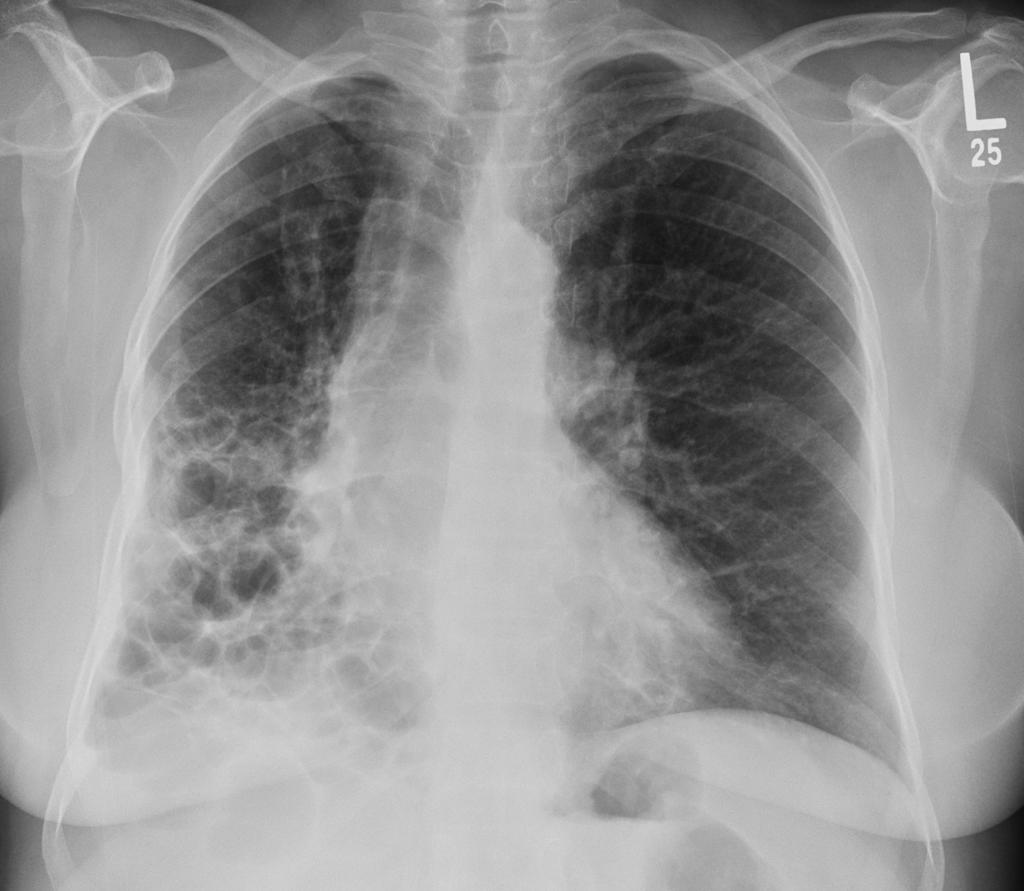

间质性肺疾病其实是一大类疾病的统称,它们的共同特点是肺部间质组织发生炎症和纤维化

当这些支架变厚变硬时,氧气就很难通过,患者会感到呼吸困难,咳嗽不止